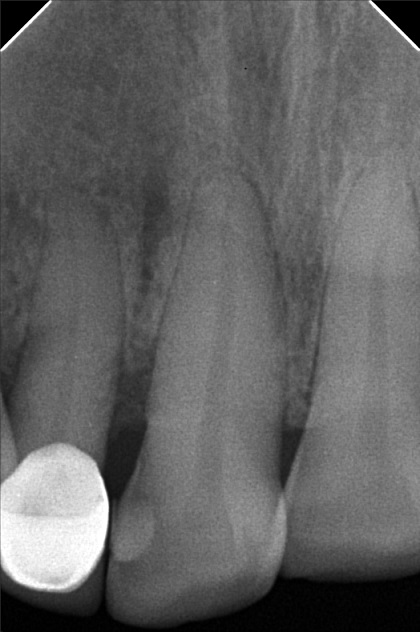

- 6/1/22- perio Tx / deep scaling laser curettage/ laser hypersensitivity/ next meeting FIRST WK august ***for change crown 9/10/22- stain removal 9/17/22 - check up for change crown

- rosario_02.jpg